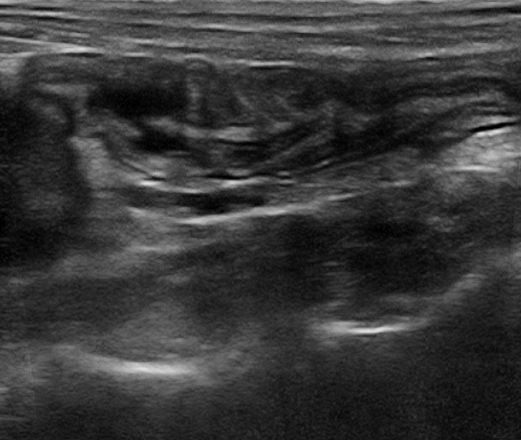

- Foi realizado exame ultrassonográfico abdominal que revelou presença de discreta quantidade de líquido livre em cavidade abdominal, linfonodos esplênico e mesentéricos acentuadamente aumentados e de ecotextura heterogênea. Visibilizou-se uma estrutura parenquimatosa aderida a um segmento de alça intestinal jejunal, homogênea, de formato ovalado, medindo 2,14cm x 1,44cm, vascularizada ao Doppler colorido e que invadia e obstruía parcialmente o lúmen intestinal, sugerindo processo neoplásico.

- Após uma semana foi realizado um novo exame ultrassonográfico para coleta de material citológico guiado pelo ultrassom. Neste novo exame a estrutura parenquimatosa havia aumentado de dimensões (2,96cm x 1,95cm), alguns segmentos de alças intestinais apresentaram plissamento e espessamento de parede. O fígado apresentou-se hipoecogênico e os linfonodos mesentéricos e esplênico permaneciam aumentados e heterogêneos.

Veja as imagens dos exames abaixo:

Estrutura em alça 1º exame

Estrutura em alça 2º exame